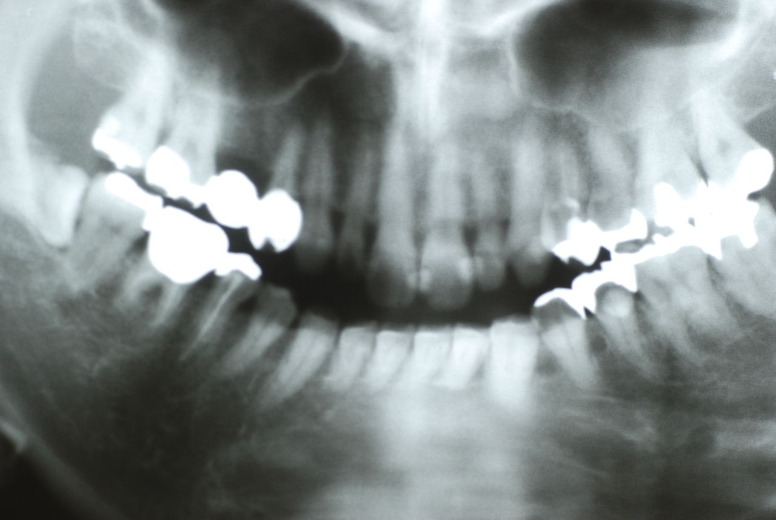

隣の14歳大臼歯がひどい虫歯になり治療不可能になりつつある状態のレントゲン